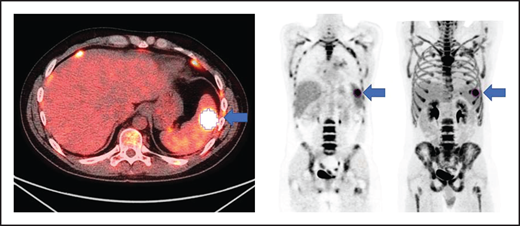

All patients had baseline 18F-FDG PET/CT scans before lymphodepletion and CD30.CAR-T cell infusion. In patients who had a 18F-FDG PET/CT prior to bridging therapy, these scans were evaluated for MTV to provide a tumor burden comparison before and after bridging therapy. 18F-FDG PET/CT scans were evaluated using MIM 7.0.5 (MIM Software, Cleveland, OH). MTV was computed using the threshold tool in MIM with a threshold 41% of the maximum standardized uptake value (SUV), or SUVmax, as described elsewhere.10-14 The lesion was manually selected and the region of interest increased until all voxels at least 41% of the SUVmax (Figure 1). MTV for each patient was determined by summing the volumes of lesions with voxels at least 41% of the SUVmax.

Axial fused, coronal PET-only, and maximum intensity projection images. Representative lesion segmented using 41% of SUVmax as cutoff (blue arrows).